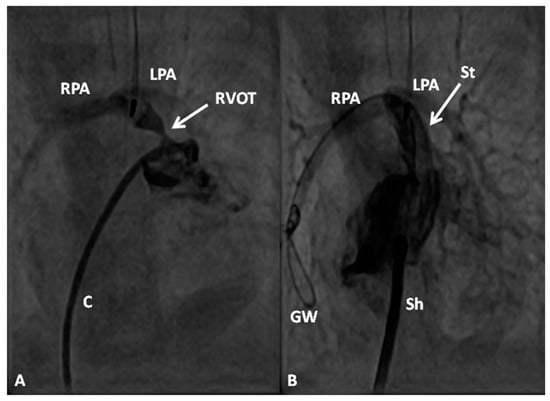

In premature babies two different palliative procedures were used as a bridge to total correction later. Balloon pulmonary valvuloplasty has been used in premature babies with TOF and significant arterial desaturaion as a bridge to total correction [17]. Similarly, deployment of a stent in RV outflow tract (Figure 3) may be used to promote growth of the pulmonary arteries and facilitate complete surgical correction at a later time [18].